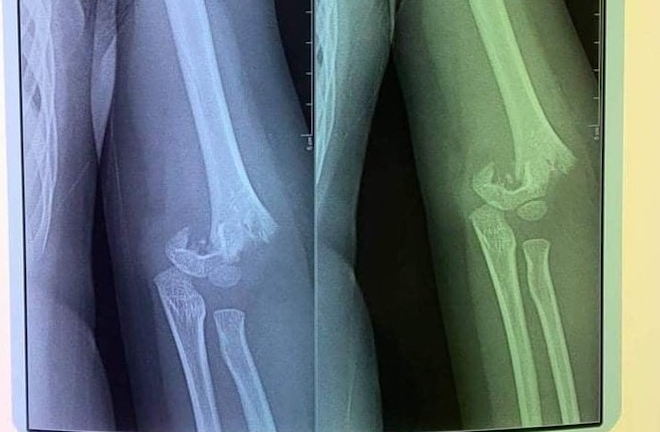

Bệnh viện Đa khoa Hùng Vương (Phú Thọ) vừa tiếp nhận và cấp cứu cho nam thanh niên 28 tuổi nhập viện trong tình trạng đau nhiều, biến dạng, mất vận động khuỷu tay phải.